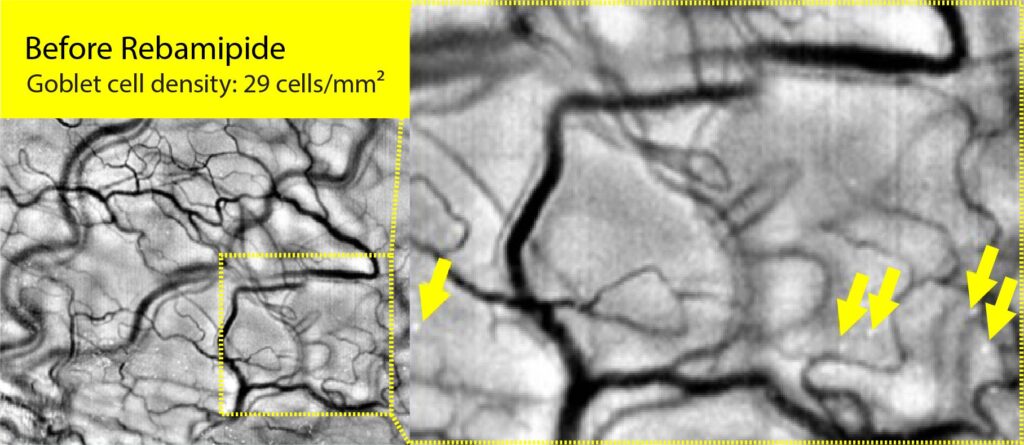

술잔세포는 결막 상피에서 점액 성분인 MUC5AC를 분비하여 눈물막의 점액층을 형성하며, 눈물의 안정성과 안구 표면의 윤활을 유지하는 데 핵심적인 역할을 합니다.

우리는 세계 최초로 결막 술잔세포 영상화 기술을 개발, 안구건조증을 포함한 다양한 안과 질환의 진단에 활용할 수 있는 핵심 기술을 개발. 술잔세포는 안구건조증 등의 확실한 바이오마커로, 면역 관용성 유지에도 중요한 역할을 하며, 이를 기반으로 다른 질병 진단 기술로도 확장 가능

고해상도 영상 데이터를 기반으로 한 AI 기반 분석 기술을 통해 진단의 정확도와 효율성을 지속적으로 개선하고 있으며, 특히 안구 내 백혈구 움직임, 술잔세포 밀도, 혈관 패턴 등 미세 영상 정보를 머신러닝 모델에 학습시켜 다양한 안과 질환 및 자가면역·염증성 질환과의 연관성을 규명하고자 합니다.이를 위해 소프트웨어 및 AI 인프라 영역에 대한 투자를 강화하고 있으며, 향후에는 AI 진단 알고리즘의 적용 범위를 전신 질환 평가 및 약물 반응 예측 등으로 확장해 나갈 계획입니다.